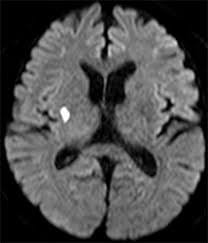

2.頭部MRI:磁力を使って脳の画像を作成します。(X線の被ばくはありません。)

MRIは急性期の脳梗塞(下図の白い小さな病変)を判定でき、急性期の脳出血も判定可能です。撮影時間は撮影内容によって異なりますが、約20分です。